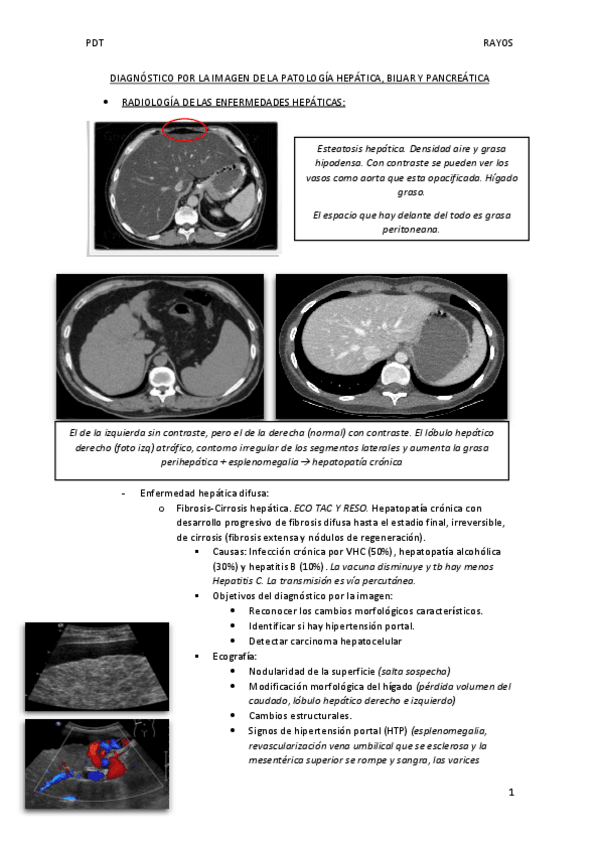

TEMA-RAYOS-HIGADO-PANCREAS-Y-VIA-BILIAR.pdf